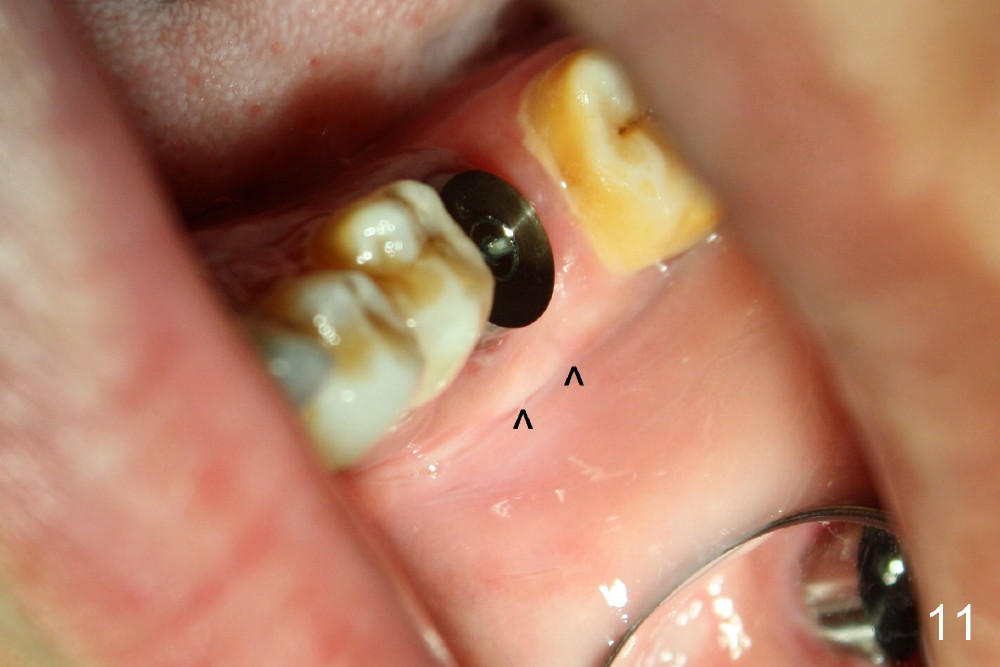

When 7x17 mm tap is placed, it drops mainly into the mesial socket (Fig.8). The septum appears to have been pushed to the distal one (<). When the 7x17 mm implant is placed with primary stability, the top portion is in the middle of the edentulous space (Fig.9). Sutures are placed mesial and distal to close the socket (Fig.10). The wound heals normally 3 months postop (Fig.11: ^). There is no bone resorption; the bone density on the top of the distal socket increases (Fig.12: D). The crown is fabricated 1 month later.